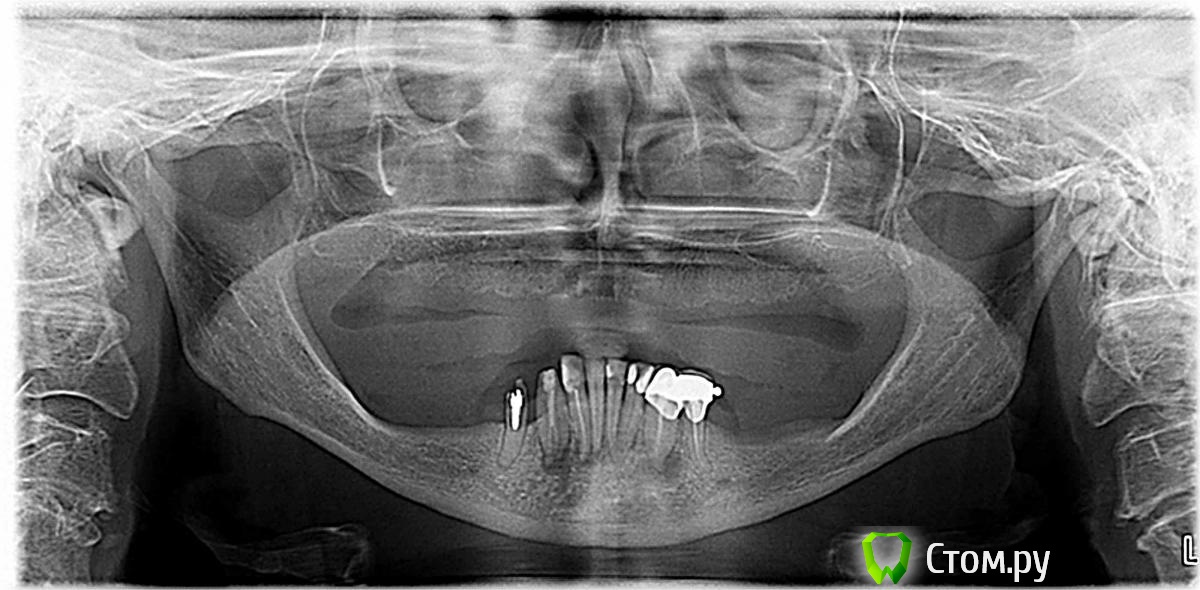

Луша Опубликовано 28 января, 2014 Поделиться Опубликовано 28 января, 2014 Добрый день! Хочу поставить импланты, была на консультации у врача и после просмотра ОПГ он сказал сколько нужно имплантов .Но меня смутил один момент, что не нужна костная пластика зубы удалены уже давно и нижняя челюсть совсем маленькая.Вопрос возможно ли это,? Посоветуйте вариант и план лечения Ссылка на комментарий